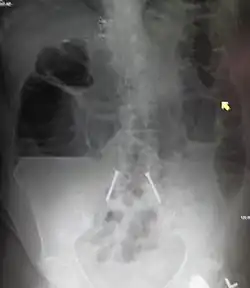

As causas de obstrução intestinal incluem aderências, hérnias, vôlvulos, endometriose, doença inflamatória intestinal, apendicite, tumores, diverticulite, colite isquémica, tuberculose e intussuscepção.[3][1] As obstruções do intestino delgado ocorrem mais frequentemente devido a aderências e hérnias, enquanto que as obstruções do intestino grosso ocorrem mais frequentemente devido a tumores e vôlvulos.[3][1] O diagnóstico pode ser feito através de radiografia simples; no entanto, a tomografia computadorizada geralmente proporciona maior precisão.[3] Os dispositivos ultrassónicos ou de imagem por ressonância magnética também podem ajudar no diagnóstico de crianças ou mulheres grávidas.[3]